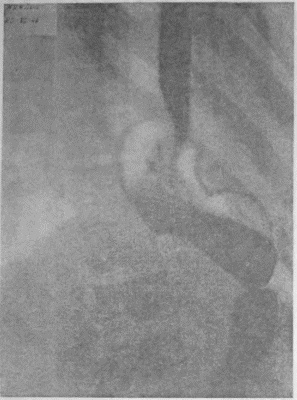

Если при локальном раке кардии и нижнего конца пищевода можно ограничиться все же экономной резекцией фундального отдела, то при более обширном раке или опухолях, захвативших немалую часть верхней трети малой кривизны, иногда возникает вопрос о целесообразности оставления антральной культи взамен тотальной гастрэктомии с трансторакальным соустьем пищевода и тощей кишки. Мотивы для этого могут быть двоякие. Первый и, конечно, главный — это радикальность самой резекции. Вопрос ставится так: да стоит ли сохранять антральный отдел желудка, рискуя, что в нем останутся пока еще невидимые раковые очаги; не вернее ли убрать весь желудок целиком и анастомозировать с тощей кишкой? Не создает ли тотальная гастрэктомия все же большую гарантию от рецидива? Я несколько раз видел отчетливую диссеминацию раковых узелков по передней и задней стенке желудка в радиальных направлениях, исходящую от строго локальной карциномы кардии. Это понуждало резецировать желудок в дистальном направлении весьма широко, оставляя лишь совсем маленькую антральную культю, которую удавалось все же подвести вверх в средостение и там легко анастомозировать с пищеводом тотчас ниже дуги аорты. На прилагаемых рентгенограммах (рис. 95—102) можно видеть, что небольшая культя желудка хорошо подтягивается кверху и прекрасно располагается в заднем средостении на месте иссеченного пищевода. Но каждый раз остается и тревожная мысль, как бы не получилось рецидива именно в этой сохраненной части желудка, поскольку рак проявил склонность к узелковому распространению по самой желудочной стенке. Второе соображение, которое выдвигает мысли о тотальной гастрэктомии, это опасение, что содержимое оставляемой дистальной половины желудка после пересечения обоих блуждающих нервов будет плохо эвакуироваться и тем доставит серьезные неприятности в ближайшем послеоперационном периоде. На моем личном опыте я пока еще не имел такого осложнения, но в нашей клинике однажды наблюдался больной, у которого эвакуация содержимого из оставленной антральной культи была чрезвычайно плохой в течение многих дней после операции. При этом создавалось впечатление, что полная атония оставленной части тела желудка сочетается с выраженным спазмом привратника, который не пропускал принятого бария в двенадцатиперстную кишку. Хотя, в конце концов, все наладилось и больной выписался в хорошем состоянии, однако тревог с ним было очень много. ![]() Рис. 95. ![]() Рис. 96. ![]() Рис. 97. ![]() Рис. 98. ![]() Рис. 99. ![]() Рис. 100. ![]() Рис. 101. ![]() Рис. 102. За сохранение антральной половины желудка и использование ее для прямого анастомоза с пищеводом говорит соблазнительно хорошая васкуляризация этой дистальной половины из сохраненных магистралей: аа. gastro-epiploica dextra et gastrica dextra. Насколько внимательно надо оценивать пригодность фундального отдела после лигирования обеих левых желудочных магистралей и всех vasa gastricae breves при самых высоких, надаортальных соустьях после экстирпаций среднего пищевода, настолько же после резекций проксимальной трети или половины желудка остающаяся дистальная часть превосходно васкуляризируется правыми артериальными магистралями. А это обстоятельство надежнее всего обеспечивает быстрое и прочное сращение по линии желудочно-пищеводного соустья, т. е. наиболее решающий этап всей операции. Мне могут возразить, что, анастомозируя пищевод с тощей кишкой, мы пользуемся органом, не менее богатым по кровоснабжению. Это верно, но поперечник тощей кишки не дает столько простора и пластического материала, сколько его имеется даже на короткой, но широкой антральной культе. Благодаря ширине культи имеется возможность после окончания двухрядного поперечного соустья укрыть дополнительно всю переднюю полуокружность анастомоза, сдвигая и сшивая над ним складки большой и малой кривизны. Прием этот чрезвычайно повышает прочность и герметизм соустья. А риск недостаточности последнего является главной опасностью всех подобных операций. При анастомозах с дистальной половиной желудка мы до сих пор осложнений еще не имели; зато три раза на десяток высоких резекций пищевода и анастомозов с фундальным отделом мы столкнулись с частичной недостаточностью соустья. В двух из этих случаев дело закончилось благополучно, и после вскрытия и дренажа ограниченных эмпием и срочного наложения подвесных энтеростомий для кормления пищевые свищи закрылись самостоятельно и довольно быстро. Но третий больной, врач 52 лет, хорошо перенеся надаортальную резекцию пищевода, постепенно угас, истощаясь из-за чресплеврального свища, получившегося вследствие недостаточности пищеводно-желудочного соустья. Повторяю, не только васкуляризация, но и форма оставляемой желудочной культи предопределяют качество и надежность анастомоза. Поэтому и при наложении раздавливающих гразеровских зажимов на желудок мы стремимся получить не длинную, узкую культю, а широкую, хотя бы за счет ее укорочения. Поднять высоко в средостение короткую культю можно без натяжения; зато ширина ее позволит сделать двойную боковую запашку поверх передней части законченного соустья с пищеводом. Чтобы еще уменьшить натяжение на линии анастомоза, после окончания последнего желудочную культю тщательно укладывают в заднее средостение и пришивают в нескольких местах к краям левой медиастинальной плевры. Наконец, совершенно обязательно пришить желудок к отверстию, оставляемому для него в ушиваемом разрезе диафрагмы. Напомню, что в самом начале операции, как только была вскрыта плевральная полость, n. phrenicus, всегда отчетливо видимый при переходе с перикарда на верхний купол диафрагмы, анестезируется инъекцией новокаина и раздавливается торзионным зажимом. Это создает неподвижность левой половины диафрагмы не только на время вмешательства, но и в течение нескольких месяцев после операции; таким образом, желудочная культя, вшитая в отверстие неподвижной диафрагмы, получает надежную опору и тем дополнительно исключается возможность натяжения в швах анастомоза. |